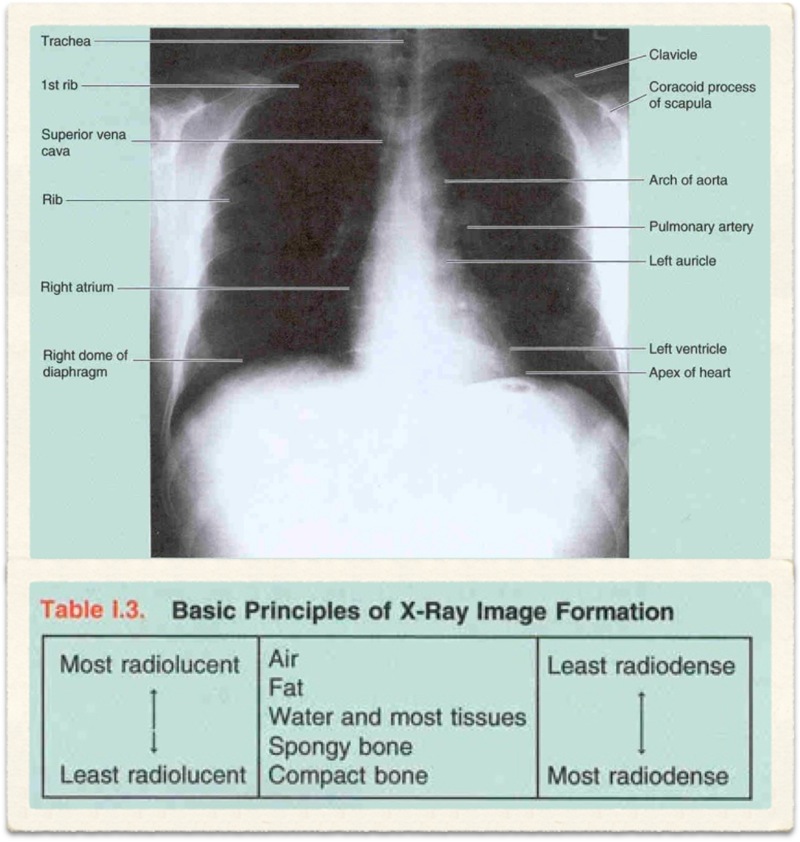

Radiological Report: Cardiac size within normal limits. Both lungs show severe overinflation typical of COPD. No sign of mass or consolidation.

Hyperinflation secondary to emphysema

Chronic bronchitis cannot be diagnosed radiologically. Although findings such as increased lung markings or tubular opacities, bronchial wall cuffing (thickening) can be seen with bronchitis, they are nonspecific. The main reason for getting a chest X-ray is to exclude other conditions, such as bronchiectasis, which can mimic the disease clinically.